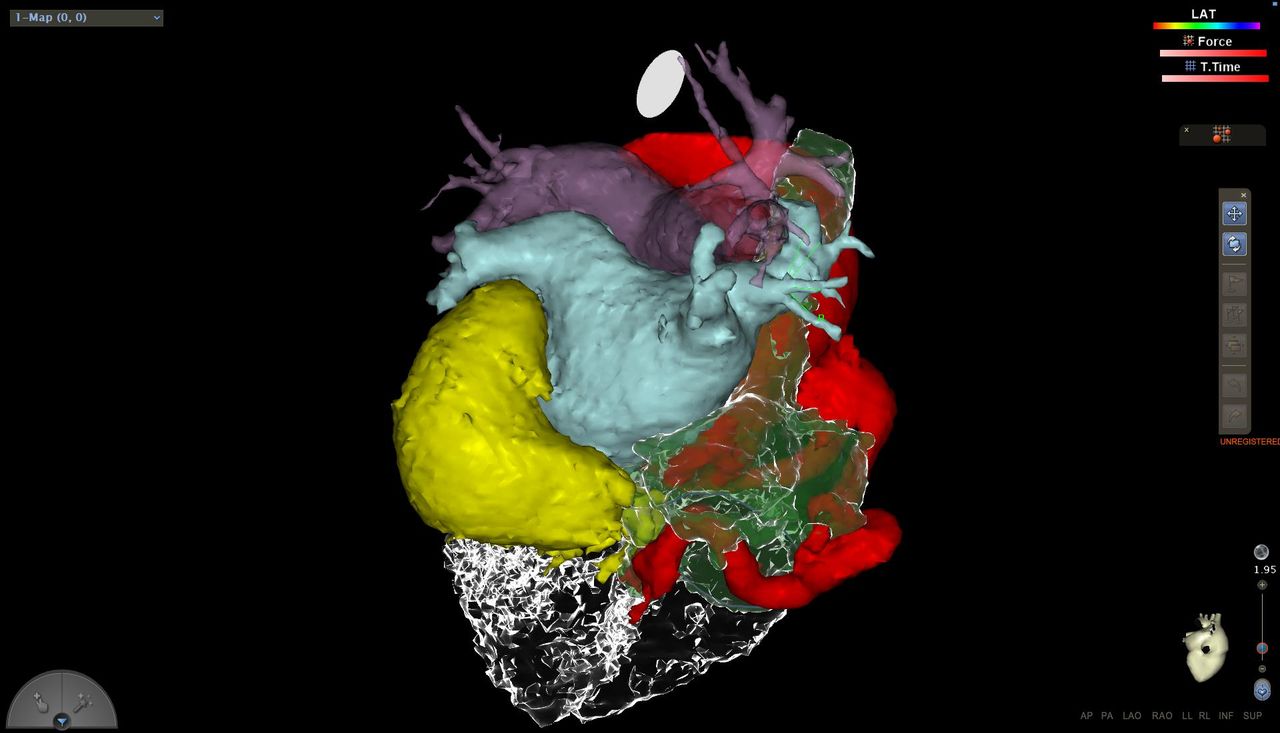

Effettua procedure di ablazione transcatetere e studi elettrofisiologici endocavitari per la diagnosi e il trattamento delle aritmie cardiache, esegue inoltre impianti di pacemaker, defibrillatori e dispositivi di resincronizzazione cardiaca per il trattamento dello scompenso cardiaco.